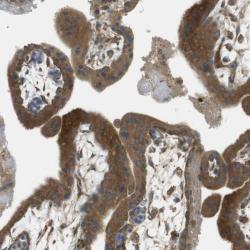

Supportive validation

- Immunohistochemical staining of human placenta shows strong cytoplasmic positivity in trophoblastic cells.

- Validation comment

- Staining pattern partly consistent with experimental and/or bioinformatic data.